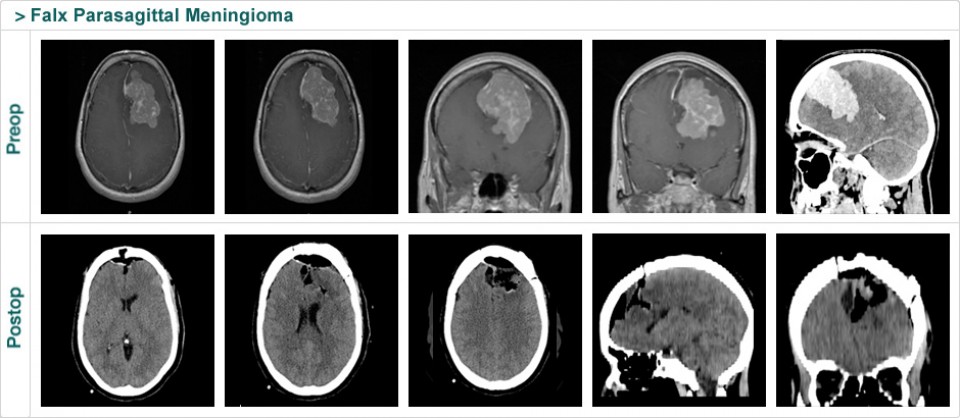

Dr. Attia is an attending neurosurgeon and the director of skull base surgery service in the department of neurosurgery at Sheba Medical Center in Tel HaShomer. His specialty focuses on skull base and cerebrovascular neurosurgery.